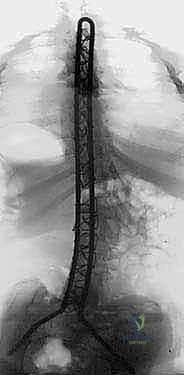

Radiographic evaluation must be exhaustive. Standard full-length standing or sitting anteroposterior (AP) and lateral radiographs are obtained to measure the primary Cobb angles, regional kyphosis/lordosis, and the degree of pelvic obliquity. However, the most critical imaging for surgical decision-making is the supine traction or side-bending radiograph. These dynamic films dictate the flexibility of the curve. If the curve remains rigid (correcting less than 30-40%) or if the pelvic obliquity cannot be leveled passively, the surgeon must plan for extensive posterior column osteotomies (Ponte osteotomies) or, in severe cases, a staged anterior release.

Neuromonitoring, utilizing Somatosensory Evoked Potentials (SSEPs) and Motor Evoked Potentials (MEPs), is standard of care. However, the surgeon must recognize that baseline signals in severe CP or myelomeningocele patients are often degraded or entirely absent. A robust blood conservation strategy must be implemented prior to incision, including the prophylactic administration of Tranexamic Acid (TXA), utilization of intraoperative cell salvage, and ensuring the immediate availability of type-specific cross-matched packed red blood cells and fresh frozen plasma.

The correct width of the U-rod is selected to sit comfortably across the laminae. The rod is then introduced to the sterile field. The distal limbs are simultaneously impacted into the bilateral iliac holes. At this stage, the proximal U-portion of the rod will be standing high above the thoracic spine due to the uncorrected deformity.

5. The Cantilever Reduction Maneuver

With the pelvis securely docked, the cantilever reduction begins. The surgeon forcefully pushes the proximal U-portion of the rod down toward the thoracic spine. This maneuver requires significant physical force and utilizes the rod as a massive lever arm.

As the rod is brought down to the spine, it translates the apical vertebrae toward the midline, correcting the scoliosis, while simultaneously forcing the elevated hemi-pelvis down, correcting the pelvic obliquity.